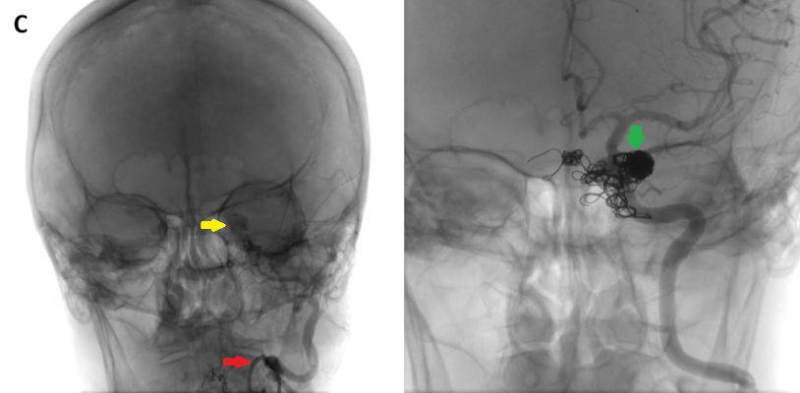

- C) DSA incelemelerinde sol eksternal karotid arter (ok) kateterizasyonunda kontrast maddenin kavernöz sinüse (ok) geçtiği izleniyor. Tedavi sonrası görüntüde kavernöz sinüs ile karotis arteriyel sistem arasında bulunan fistül traktına coil embolizasyon (ok) işlemi uygulandığı görülüyor.

- DSA incelemelerine göre fistüller direkt ve indirekt olarak sınıflandırılmaktadır.

- DSA: Fistülün akış hızını karakterize ederek direkt ve indirekt fistülleri net olarak ayırabilir. ICA defektinin tam anatomik yerini ve ICA veya ECA dural besleyicilerini gösterir. Ayrıca DSA ile endovasküler tedaviler yapılabilmektedir.

- Olgumuzun DSA incelemelerinde sol ICA ve ECA’dan kavernöz sinüse fistülöz bağlantı olduğu izlenmiş ve coil embolizasyon işlemi uygulanarak tedavi edilmiştir.